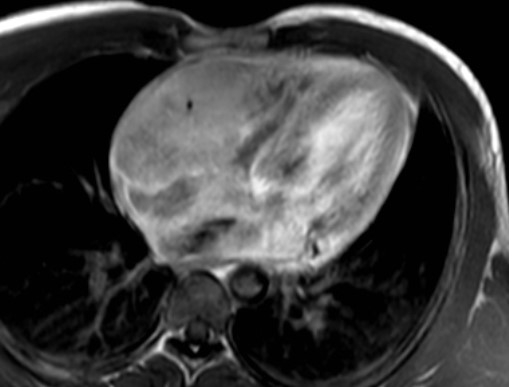

La risonanza magnetica (RM) cardiaca presentava nelle sequenze cine-SSFP (Steady State Free Precession) all’interno delle camere destre una massa ipointensa, infiltrante le pareti del miocardio, il pericardio, la valvola tricuspide, la radice aortica e la vena cava superiore (Figura 4).

linfoma_cardiaco_4.jpg

Figura 4

Infine, sulla base della RM cardiaca, la conferma dell’infiltrazione miocardica e pericardica, il rilievo della mancata infiltrazione dell'arteria coronaria destra e della scarsa vascolarizzazione, l’aspetto isointenso in T1, l’aspetto iperintenso in T2, e il lieve enhancement tardivo del gadolinio escludevano nuovamente la diagnosi di angiosarcoma, orientando al contrario verso quella di linfoma.